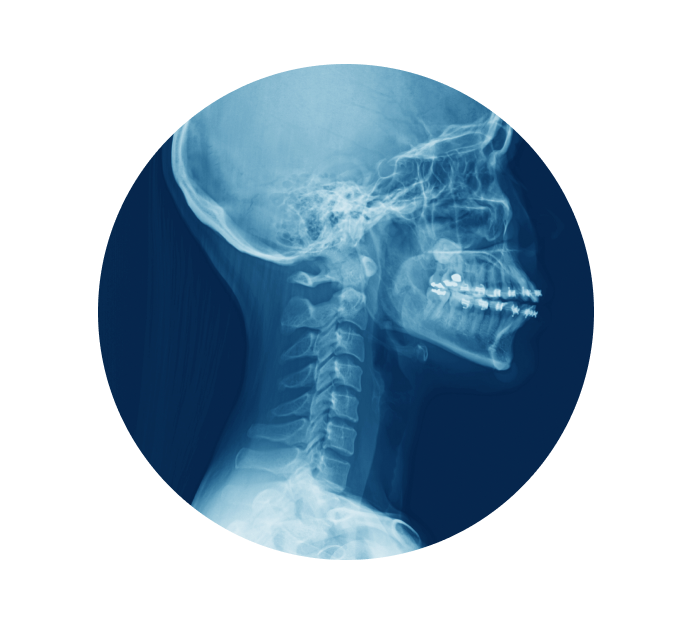

Рентген шейного отдела позвоночника в Каменске-Уральском

Рентген шейного отдела позвоночника позволят выявить такие нарушения и заболевания как остеохондроз, показывает деформацию шейных позвонков, смещение дисков, растяжение, ушиб и не только. При патологиях костных структур этой области тела нарушается ее подвижность, появляются головные боли, нарушается работа вестибулярного аппарата.